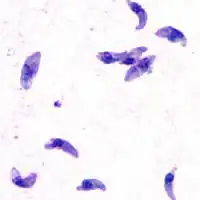

Skin

While rare, skin lesions may occur in the acquired form of the disease, including roseola and erythema multiforme-like eruptions, prurigo-like nodules, urticaria, and maculopapular lesions. Newborns may have punctate macules, ecchymoses, or "blueberry muffin" lesions. Diagnosis of cutaneous toxoplasmosis is based on the tachyzoite form of T. gondii being found in the epidermis.[31] It is found in all levels of the epidermis, is about 6 by 2 μm and bow-shaped, with the nucleus being one-third of its size. It can be identified by electron microscopy or by Giemsa staining tissue where the cytoplasm shows blue, the nucleus red.[32]